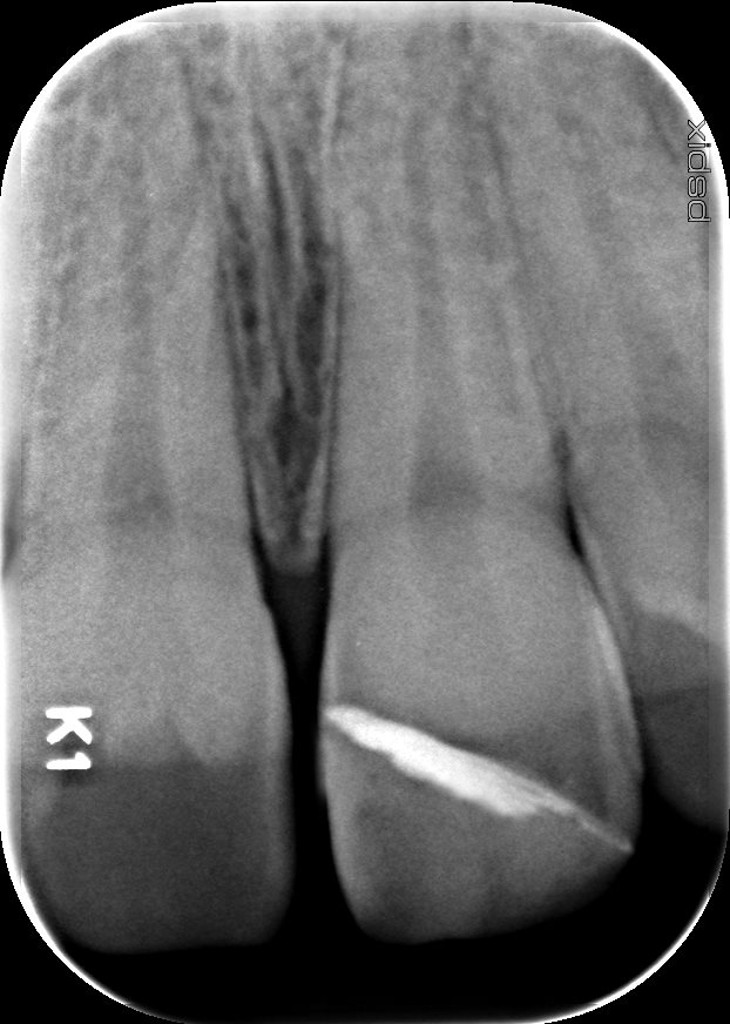

Radiographie immédiate post-op